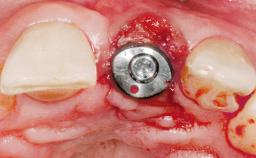

Immediate Placement of an Implant in a Maxillary Right Central Incisor Site

A 30-year-old female patient was referred to the office for the treatment of tooth 11. Her chief concern at the initial visit was to inquire, “Why is my tooth pink?” Upon clinical examination, it was determined that tooth 11 had a previous history of trauma and that the clinical crown had become noticeably pink in color as a result of internal resorption. This diagnosis was confirmed radiographically, indicating a large radiolucency involving the central and distal portions of the clinical crown. It was determined that restoration of this tooth was not possible, and that extraction was indicated. The presence of a mid-line diastema, which the patient wanted to reproduce, directed the treatment plan for tooth replacement utilizing a dental implant.

Placement Protocol Immediate implant placement

Tooth Site Maxillary incisor or canine

Socket Morphology Single-root socket

Socket Integrity Sufficient, with intact bone walls